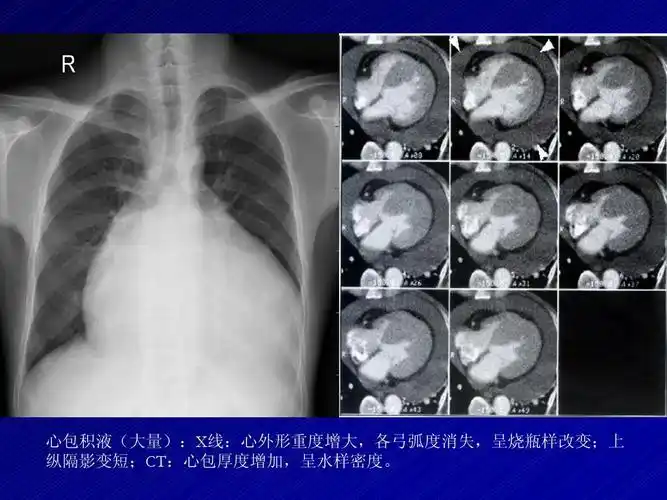

心包积液(大量):x线:心外形重度增大,各弓弧度消失,呈烧瓶样改变;上